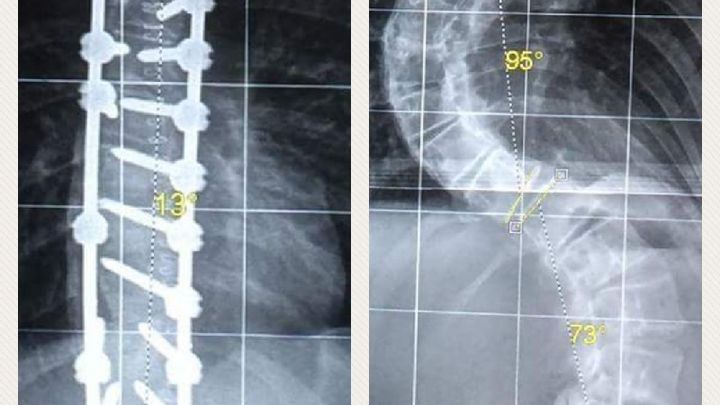

My name is Megan. I am 14 years old. I was diagnosed with Scoliosis in 2014 and it was a very fast progressing type.

Thankfully I have had my surgery and now I hope to raise awareness and funds for the condition.